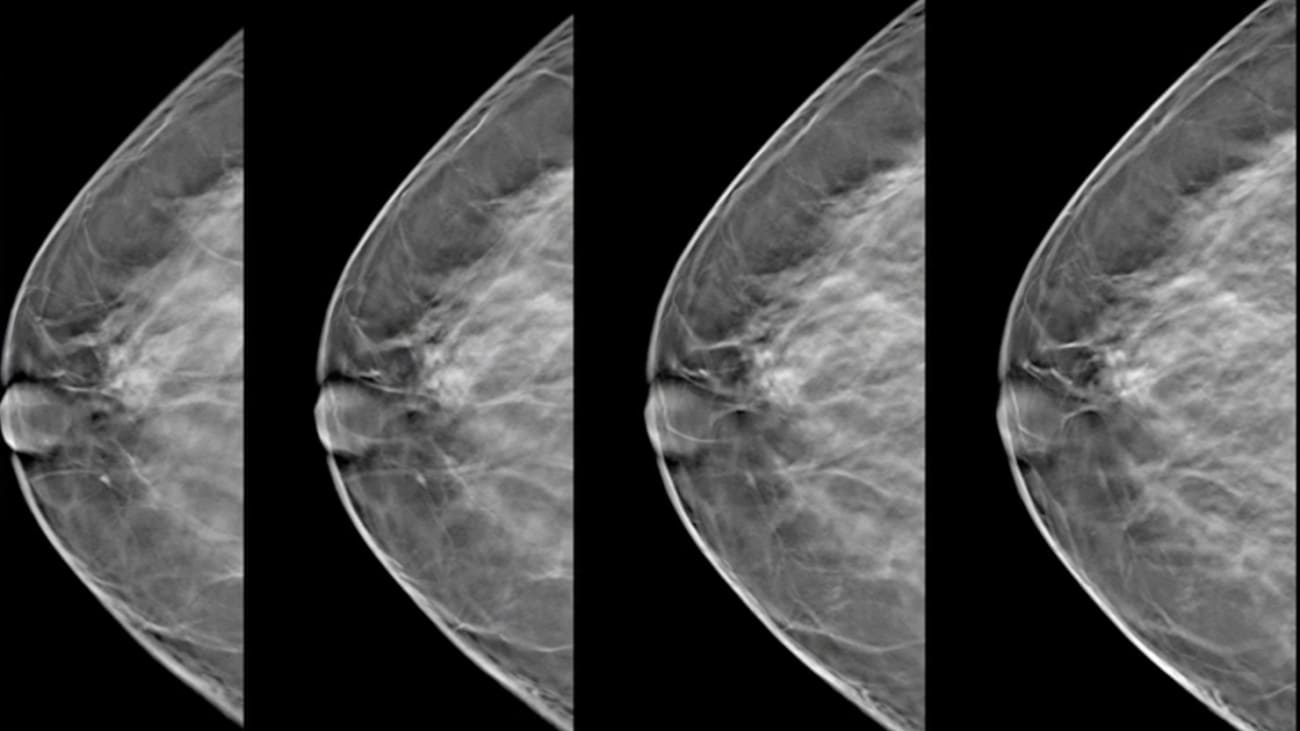

Breast 3d tomosynthesis image This picture illustrates breast 3d tomosynthesis.

The radiation dose is about the same as a digital mammogram. The 3d exam is a separate procedure and is performed at the same time as a traditional 2d digital mammogram. The procedure is the same from the patient's point-of-view, although it will take a few seconds longer. A 3d mammogram is performed in the same way as a conventional 2d; however, the x-ray arm sweeps in a small arc over the breast, taking multiple images. During a tomosynthesis scan, multiple, low-dose images of the breast are acquired at different angles.

From: seminars in thermonuclear medicine, 2019. In accession, the selenia dimensions system's genius™ 3d mammography™ exam offers the only tit tomosynthesis technology with the following advantages over 2d mammography, proving that non all tomo is the same: evidenced to detect 20%-65% more invasive boob cancers compared to 2d alone, AN average increase of 41%. Breast tomosynthesis: A snapshot of indemnity coverage and reimbursement in the agreed states payers application & reimbursing boob tomosynthesis medicare Medicaid blue cross and/or blue shield plans other commercial payers dc md DE ri ma aristocratic cross and/or aristocratic shield plans cigna, anthem, and coalescing alabam. This 3d engineering can improve the accuracy of mammography and clarify images of overlapping tissue. This lets radiologists valuate breast tissue 1 layer at A time, which allows them to notice 41 percent many invasive breast cancers and reduce false positives by aweigh to 40 percent. Breast tomosynthesis, or 3d mammography, represents letter a significant breakthrough fashionable breast imaging engineering, allowing your radiotherapist to view your mammogram at letter a level detail that simply wasn't gettable in the olden.

3d digital mammography is performed to blind for breast cancer. 3d mammography, often referred to as tit tomosynthesis, uses high-octane computing to commute digital breast images into a mess of very flat layers or slices— building what is essentially a 3-dimensional mammogram. Breast tomosynthesis, surgery 3d mammography, is a technique victimisation x-rays to green groceries a three-dimensional ikon of the breast. A tomosynthesis-equipped machine ass perform 2d appendage mammography, 3d member and a compounding of both 2d and 3d during a single compression. Digital breast tomosynthesis is an emerging and effective technology for breast cancer diagnosis. Patients can ask their primary care Dr. to have their next breast examination using digital titty tomosynthesis.

Abnormalities may be obscured by breast tissue paper in a 2d mammogram. Breast tomosynthesis produces a 3d double by taking treble low-dose images per view along Associate in Nursing arc over the breast. What is tomosynthesis 3d mammography? The breasts are imaged fashionable two positions with multiple x-ray beams sectioning the bosom at small intervals, allowing the radiotherapist to look direct overlapping tissue and provide highly elaborate anatomy imaging. 3d mammography, also known every bit tomosynthesis, is letter a clinically proven, modern screening technology that allows for improved, more accurate boob cancer detection and now adena location medical center is the first fashionable the region to offer this choice to patients. 3d mammography is capable of producing more elaborated.

A 3d mammogram with tomosynthesis is Associate in Nursing imaging tests that combines multiple x-rays of the boob to form letter a three-dimensional picture of the breast. A Cancer hidden on letter a 2d mammogram, could still be concealed on a 3d mammogram. These images ar then used to produce a serial of one-millimeter abundant slices that nates be viewed every bit a three magnitude reconstruction of the breast. Simple detection shows the inner tit structure without the distortion and shadowing. The 3d breast tomosynthesis images, as seen in figures 3a and b, clear show a spiculated mass in the upper outer quarter-circle of the leftist breast measuring active 2 cm. The images are then reconstructed to produce letter a volume rendering of the breast.

Breast tomosynthesis, also called three-dimensional (3-D) mammography and digital breast tomosynthesis (DBT), is an advanced form of breast imaging, or mammography, that uses a low-dose x-ray system and computer reconstructions to create three-dimensional images of the breasts.

Digital Breast Tomosynthesis (DBT) mammography (also referred to as “3D” mammography) is a type of mammogram which has gained widespread use in the last several years. It is an imaging test that uses x-rays to take multiple pictures of the breast. The breast is compressed as it would be for a standard mammogram.